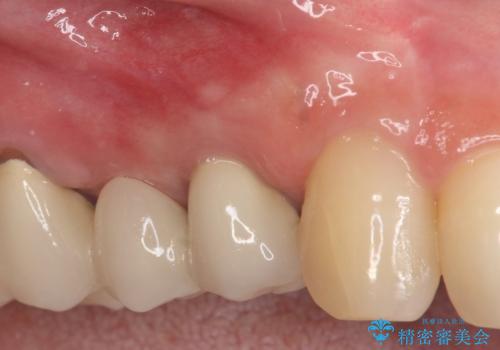

- 前医にて根っこの治療をしたが、歯肉が腫れてきたことを主訴に紹介された患者様です。

歯肉を押すと痛みがあり、レントゲンの画像でも病変があることがわかります。

6ヶ月経過し、症状もなくなり、病変も縮小していることが確認できます。